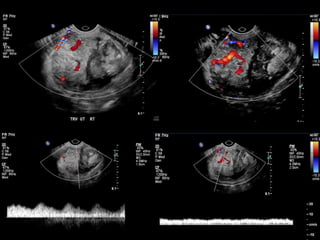

HISTORY

โ€ข 40 yo female 8.5 weeks pregant

โ€ข S/P D&C for pregnancy implanted at site of

c-section scar

โ€ข 6 weeks post D&C patient presents with

heavy persistent bleeding

โ€ข For Pelvic US

โ€ข HCG = 451 mIU/mL

HISTORY โ€ข 40 yofemale 8.5 weeks pregant โ€ข S/P D&C for pregnancy implanted at site of c-section scar

• 42.

โ€ข 6 weekspost D&C patient presents with heavy persistent bleeding โ€ข For Pelvic US โ€ข HCG = 451 mIU/mL

• 50.

D&C complicated byPerforation, AVM w RPOC at Site of Perforation โ€ข AVM โ€“ Acquired or Congenital โ€ข Acquired โ€“ Traumatic โ€“ D&C, TAB, uterine surgery โ€“ Less common: Endometrial / Cervical CA, GTD โ€“ Clue on US: numerous tortuous vessels, high velocities โ€ข Tx: โ€“ transcatheter arterial embolization โ€ข Potential to preserve fertility โ€“ UA ligation, hysterectomy